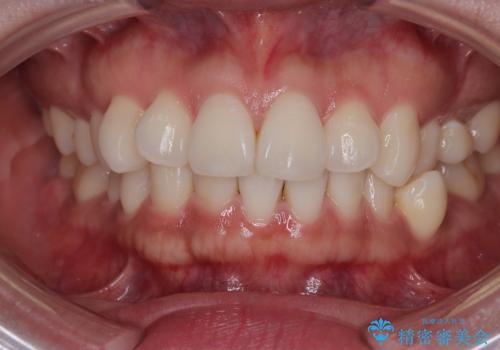

デコボコと正中のずれを改善した矯正治療

- 「歯並び全体のデコボコが気になる」「上下の歯の正中(中心)がずれているのが気になる」

このようなお悩みを主訴にご来院された患者様の矯正治療症例をご紹介します。

「歯並びと正中が整って、自信をもって笑えるようになった」

と大変ご満足のお言葉をいただきました。